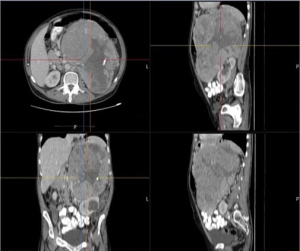

A CT scan of the abdomen with intravenous contrast showed a large, well-circumscribed, hypo-enhancing mass with necrosis; a few calcifications were seen in the left upper abdomen above the left kidney, displacing the adjacent organs and structures but with no invasion. The mass measured about 17.1 cm × 20.7 cm × 26 cm, with an indiscernible ipsilateral suprarenal gland. Splenic and left renal vein varicosities were seen with otherwise well-contrasting opacification and no filling defects. The right kidney appeared normal in size, shape, and orientation. The left kidney was normal in size and shape and was displaced inferiorly by the mass, but not invaded, and demonstrated a large, well-circumscribed cystic lesion in the mid portion measuring 5 cm × 4 cm. The radiological conclusion was that the patient had a huge left suprarenal mass with features highly suggestive of adrenal carcinoma, with no evidence of gastric or renal invasion (Figure 2). Based on the radiological findings of a large tumor confined to the adrenal gland with no evidence of lymph node involvement or distant metastasis, the tumor was classified as ENSAT stage II at initial diagnosis.